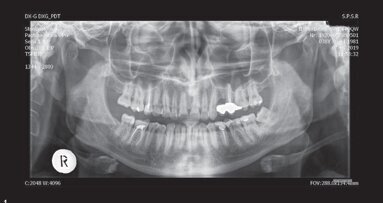

在德国,每年约有七百万例根管治疗。尽管牙科锉刀由超弹性镍钛合金制成,但在受到应力的情况下,这些锉刀容易断裂,需要经常拆卸和彻底清洁。

根管治疗 旋转镍-钛锉刀 牙髓学